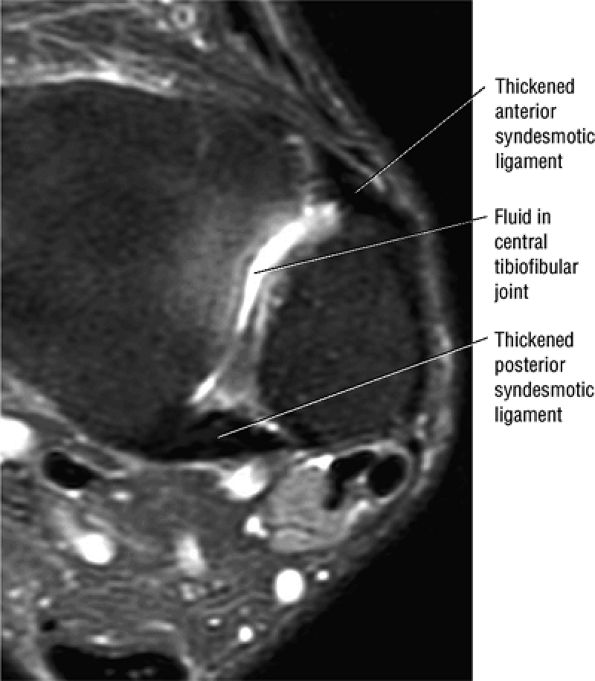

FIGURE 5.27 ● Axial anatomy of the ankle and foot. (A) The flexor digitorum longus, flexor hallucis longus, peroneus brevis, soleus, and extensor digitorum muscles are examined at this level for strain, tears, or fatty atrophy that may suggest denervation. (B) The tibialis anterior, extensor hallucis longus, and extensor digitorum longus tendons are examined on every ankle MR examination. Extensor tendon pathology is frequently overlooked if these tendons are not included as part of the ankle checklist. (C) Tears and sprains of the anterior syndesmotic ligament are a frequent cause of persistent ankle pain following ankle sprain. The syndesmotic ligaments are thick, tough ligaments that are important ankle stabilizers, and delayed diagnosis of syndesmotic tears may result in significant degenerative arthrosis at the tibiotalar joint due to the resulting ankle instability. The syndesmotic ligaments course obliquely inferiorly from the tibia to the fibula and are not usually visualized in their entirety on a single axial image; rather, their course is followed on at least two or three successive axial images. (D) The peripheral margin of the peroneal tendons and tibialis posterior tendon should normally never extend beyond the peripheral margins of the lateral and medial malleoli, respectively. Tendon subluxation around the posterior corner of either malleolus is indicative of a tear of the overlying flexor retinaculum (medially) or peroneal retinaculum (laterally). When the retinacula are torn, the tendon is free to intermittently sublux or dislocate, leading to tendon degeneration, pain, and tendon dysfunction. (E) Suspected osteochondral lesions of the talar dome are visualized and further characterized on axial images through the top of the talar dome. (F) The peroneus brevis tendon may normally appear somewhat flattened. However, as the tendon degenerates, it becomes U-shaped and drapes around the anterior aspect of the peroneus longus and becomes impinged between the peroneus longus tendon and the lateral malleolus. With further degeneration, the peroneus brevis may split or completely rupture. (G) Evidence of anterior talofibular ligament injury is visualized on the majority of MR ankle examinations and appears as thickening, intermediate signal with ill-defined fibers, or attenuation of the ligament. This is commonly asymptomatic. (H) Because the flexor hallucis longus tendon sheath communicates with the tibiotalar joint, fluid may normally be present within the tendon sheath in proportion to the amount of fluid in the tibiotalar joint. If there is fluid within the tendon sheath out of proportion to that seen in the tibiotalar joint, tenosynovitis is most likely present. The finding of flexor hallucis longus tenosynovitis should prompt a search for an os trigonum, as impingement of the flexor hallucis longus tendon between an os trigonum and the posterior tibial plafond is a common cause for FHL tenosynovitis. (I) The calcaneofibular ligament (CFL) passes anterior and medial to the peroneal tendons. On the image at which the CFL passes directly medial to the peroneus brevis tendon, the appearance of the peroneus brevis and the CFL side by side is occasionally mistaken for a split peroneus brevis tendon. (J) Dilated posterior tibial veins within the tarsal tunnel occasionally compresses the tibial nerve. In the setting of clinical suspicion for tarsal tunnel syndrome or if there is evidence of muscle denervation on MR images, the size of the posterior tibial veins should be described. (K) The spring ligament is identified at this axial image location, extending from the anteromedial calcaneus to the posteromedial navicular. Tears of the spring ligament may result in medial instability and hindfoot valgus. (L) The posterior tibialis tendon (PTT) may normally become thickened and fan-like as it passes posterior to its navicular insertion (prior to also inserting on the cuneiforms and the base of the second through fourth metatarsals). In the absence of other findings, the thickening of the PTT at this level should not be mistaken for focal tendinosis. (M) On inferior images through the ankle, Lisfranc's ligament is occasionally included in the FOV. Lisfranc's ligament extends from the medial cuneiform to the base of the second metatarsal. If Lisfranc's ligament is included in the FOV, the status of the ligament should be described, as undiagnosed Lisfranc ligament tears can lead to debilitating midfoot arthrosis. (N) As the medial and lateral tendons turn from their vertical course to a horizontal course along the plantar aspect of the foot, the tendons may demonstrate a magic-angle artifact, causing the tendons to appear gray on short-TE images, mimicking tendinosis. Correlation with images using longer TE values is advised in such situations.

FIGURE 5.43 High Ankle Ligaments.